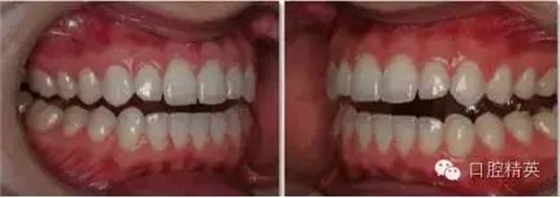

上下頜牙列照

側面觀

1:2 (1:3)放大倍率

需要使用拉鉤

•上下頜牙應輕微張開使得切端清晰可見。這樣有利于切緣平面喝切緣楔狀隙的分析。

•露出盡量多的牙齦。對稱放置拉鉤,以免造成傾斜的假象。將拉鉤向遠離牙齒的方向拉。

•盡量減少相片中嘴唇及拉鉤的影像。

•待治療的牙齒及周緣組織應能清晰可見。牙齦高度及輪廓應不被遮蓋。

•縱向中線應為側切牙的中線。

•相片的水平中線為切緣平面,垂直于縱向中線。再現天然牙的不對稱性

•焦點應位于側切牙處。選取適當的景深(通過高F值獲得)使得盡可能多的牙齒在焦距內。舌頭應往后縮,以免遮擋牙面。保持1:2(1:3)放大倍率。

•此視角并非矢狀面,因此對側的中切牙,甚至是側切牙、尖牙應能在照片中顯示。 緊記照片的中心應為側切牙。

•如果拉鉤的放置位置及合理地取景,遠離相機側的軟組織應能遮蓋大部分背景區(qū)域。